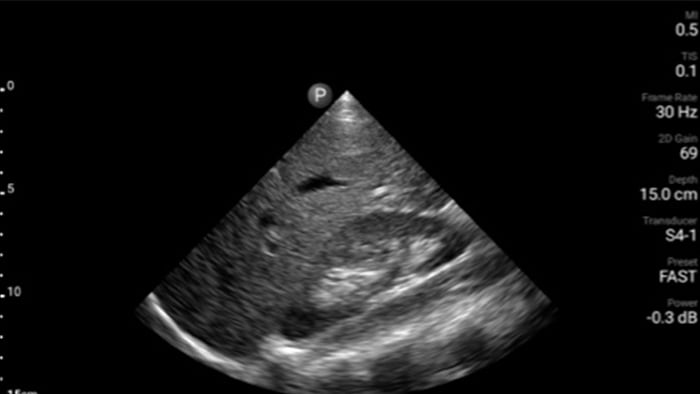

Pacientes com infarto precisam de atendimento imediato. As predefinições cardíacas do Lumify podem ajudar os pacientes a ser diagnosticados mais rapidamente para melhorar seus resultados.

• Faixa de frequência operacional de 1 a 4 MHz • Captação de imagens em 2D, Doppler colorido e pulsado*, modo-M, XRES avançado e imagem harmônica • Diagnóstico por imagem de alta resolução para aplicações abdominais, cardíacas, ginecológico/obstetríco, FAST e pulmonar. • Disponivel em Android

Exame de Avaliação Focada com Ultrassonografia em Trauma (FAST)